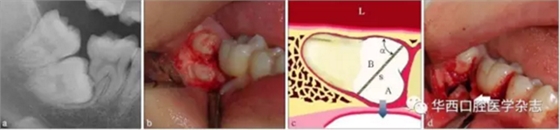

這個(gè)實(shí)際上是最簡(jiǎn)單的運(yùn)動(dòng)力學(xué)原理,物體 O受到周圍物體的抱持緊固而不易脫位,為了便于脫位,可以通過(guò)切割,人為地形成一個(gè)斜面,而沿著這個(gè)斜面, A將非常容易脫位,斜面越大,內(nèi)摩擦角α越小,阻力越小。而 A脫位后, B就失去了周圍組織的抱持緊固而易于脫位(圖 1)。具體操作時(shí),需要根據(jù)操作的可及性,靈活設(shè)計(jì)斜面的方向,必要時(shí)可多次分牙。

阻生的 47已造成 46遠(yuǎn)中牙根部分吸收(a),手術(shù)入路較為狹小而受限(b)。為了解除 47脫位阻力,對(duì)牙體進(jìn)行分割(c)。將 47牙切割成A和B,A部分因斜面(s)的存在可沿藍(lán)色箭頭方向順利脫位,并為 B部分的松解創(chuàng)造空間,松解后的 B部分可通過(guò)多次分割取出(d)。如此可以盡量減少開(kāi)窗去骨量,多保留鄰牙頸緣的骨質(zhì)(白色箭頭)。α:內(nèi)摩擦角;L:舌側(cè)。

圖1 斜面原理